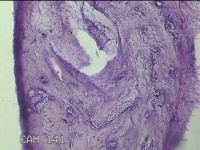

子宫肌瘤结节

多发性子宫肌瘤 继发性不孕症 子宫Ⅰ度脱垂 高脂血症 胆囊息肉

一般病史

发现子宫肌瘤4年余,继发不孕3年。

标本名称

大体所见

灰白暗红色圆形肿物10x9x2.8㎝九个,表面糜烂,切面均为灰白色结节状或编织状,质中。

良性病变。

考虑平滑肌瘤。